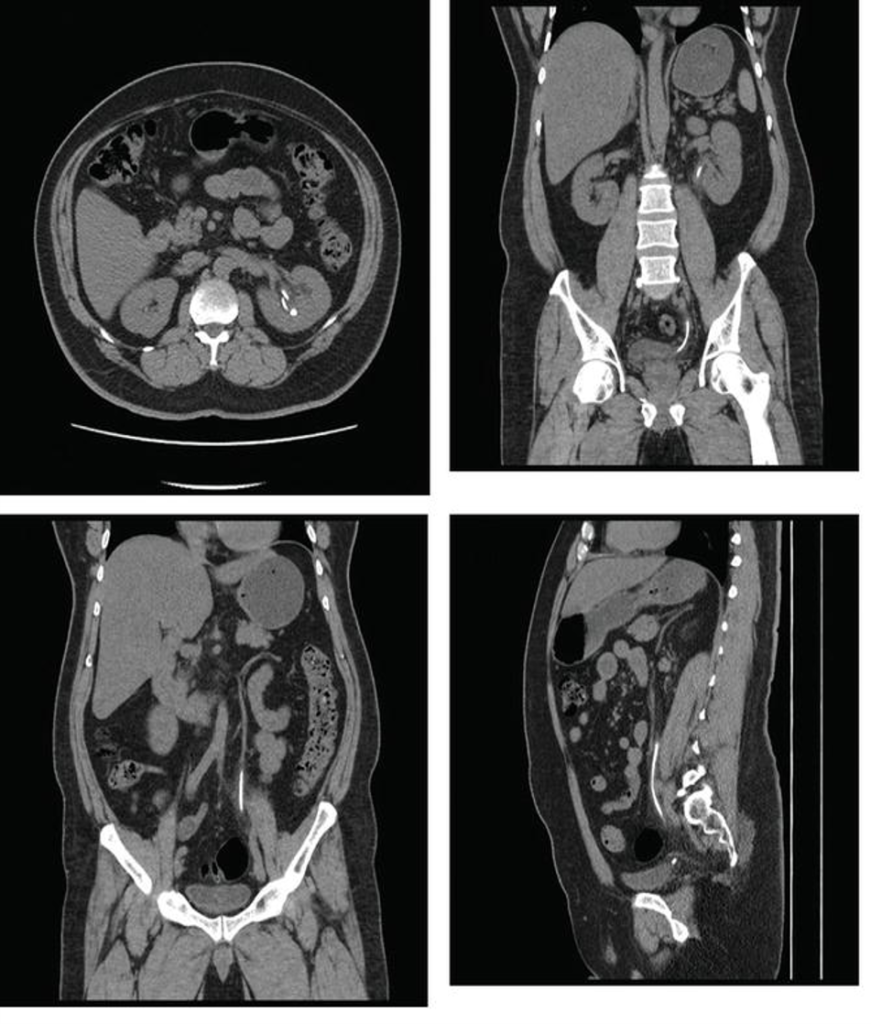

Non-contrast axial CT image showing renal stone.

Ureteric Calculus:

CT KUB axial and coronal sections demonstrating an obstructing right proximal ureteric calculus.

1)Hyperdense focus along ureteric course.

2)Soft-tissue rim sign favors stone over phlebolith.

3) Associated with Upstream hydroureter & hydronephrosis.

CT KUB axial and coronal sections demonstrating a left renal pelvis calculus (a and b) and left distal ureteric calculus (c).

Plain CT KUB showing right staghorn and giant bladder calculus measuring 9.5 × 9.4 × 11.1 cm³.

- Large branching calculus occupying renal pelvis and calyces.

- Usually composed of struvite.

- Associated with recurrent UTI.

- Suggests long-standing disease.

View of perirenal fat stranding in non-contrast computed tomography.

(a) Hydronephrosis (*), reduced peripelvic fat (white arrow) and increased perinephric fat stranding (black arrow) as compared to contralateral side.

(b) CT KUB axial, sagittal and coronal sections demonstrating multiple calcific densities near the bulbar urethra likely representing urethral diverticulum with stone formation.

CT KUB axial, coronal and sagittal sections demonstrating a calculus in the prostatic urethra.

CT KUB axial supine and prone positions demonstrating a left-sided VUJ calculus.